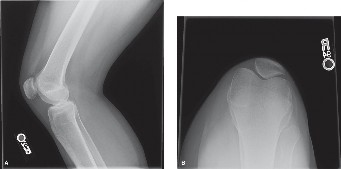

CASE 4 A 54-year-old skier injures his right knee on the last run of the day. …

CASE 2 An 18-year-old soccer player injures her knee during competition. She r…